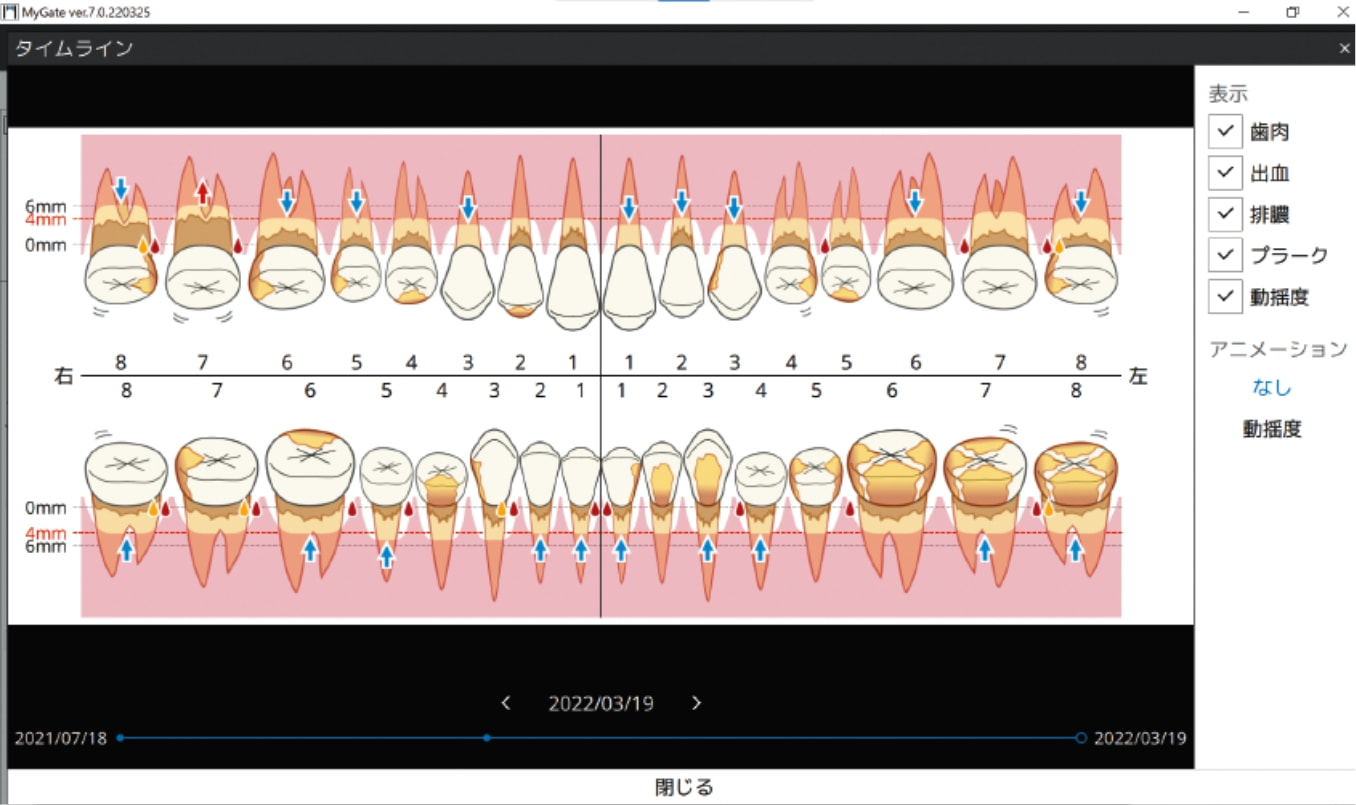

タイムライン表示

過去から現在までの口腔内データを時系列で追跡し、変化の積み重ねを“見える化”することで、診断はもちろん、予防・メンテナンスの説明も支援します

ライフタイムチャート表示

患者さんの一生涯に渡るレントゲンや口腔写真等を、部位ごとに時系列に沿って一覧で配置。

撮影の間隔や頻度を、直感的に把握できます